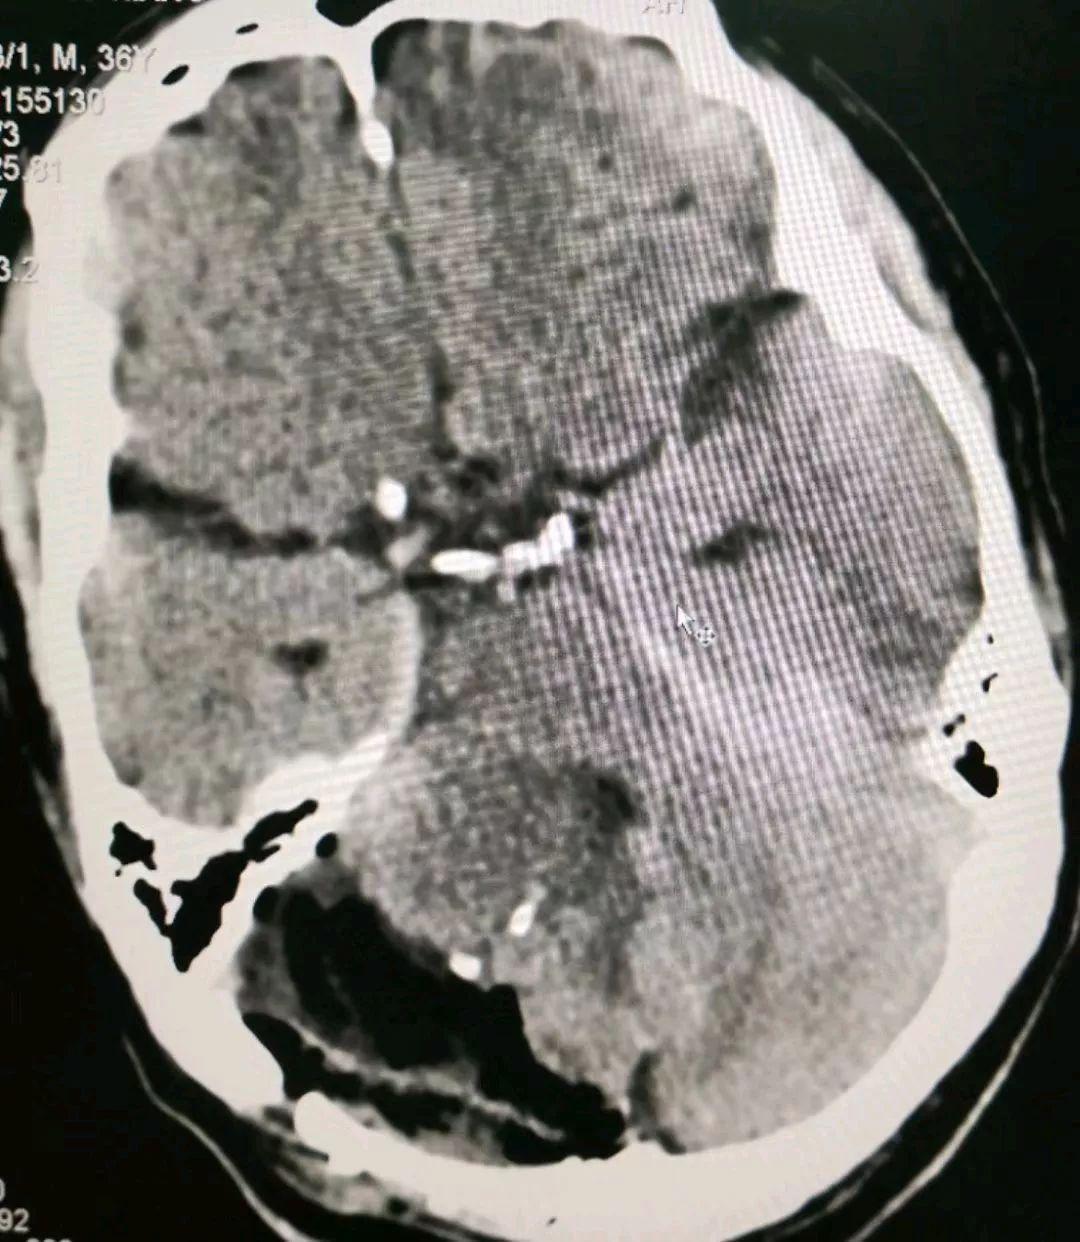

栓塞后当天顺利切除肿瘤,术中出血只有300ml,手术非常顺利。患者今日术后第3天,无任何并发症。

患者今日术后第8天,神志清楚,没有头痛头晕不适,进食正常,大小便正常,思维灵敏,语言流利,四肢活动好,准备近日出院。